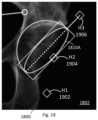

FIG.19 illustrates an enlarged portion of theGUI1800showing cup implant1810A and in which the input has been received to select or invoke a control therefor (e.g. by selecting the cup implant in the GUI 1800) to change the position of the cup implant. In accordance with the computer implemented method the GUI may be configured so that the cup overlay CI in any of the image views can be adjusted (moved) using handles on the respective objects (FIG.19). Using the handles in one image moves the CI accordingly in all images, preferably in near real time to avoid any lag or negative user experience. The cup implant can be adjusted in size (bottom floating handle H11902), anteversion (middle handle H21904), or inclination (top handle H31906).

Alternatively or in addition, the cup overlay in the images may be adjusted (moved) by inputting new values into the measurement text boxes to change an angle. The CI position is then adjusted in all images using the image co-registrations.